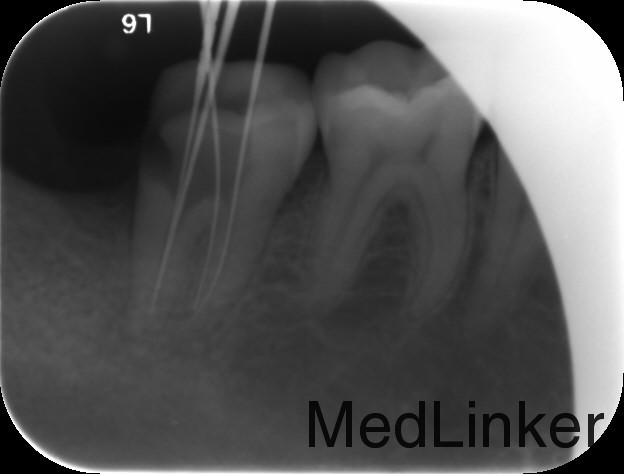

诊断:47牙髓炎 治疗计划:47根管治疗后冠修复。 处置:47碧蓝麻醉下,去腐,降牙合,开髓,揭髓,EDTA伴随下根管预备,冲洗,超声荡洗,干燥,激光消毒,封氢氧化钙。二次复诊:冲洗,试尖,AHplus糊剂和热牙胶充填。